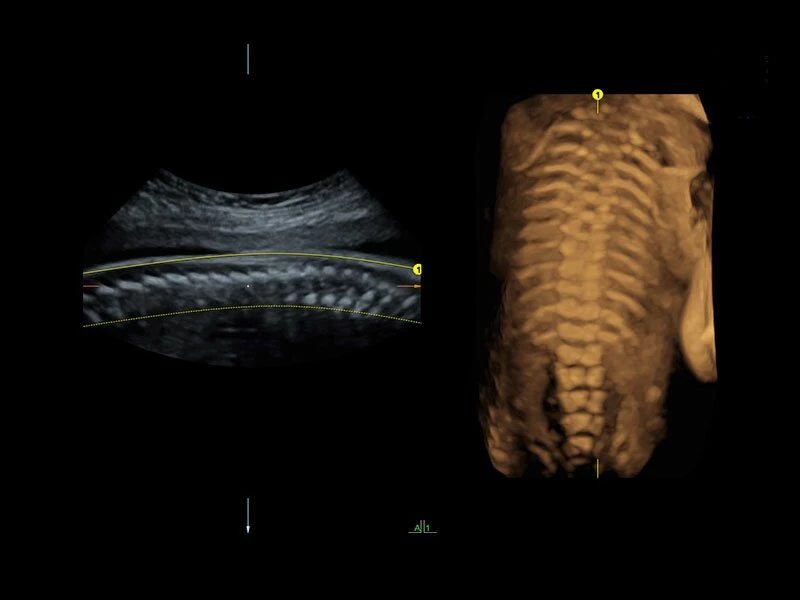

- Скелетно-мышечная система;

Voluson E10 — это новый уровень беспрецедентного качества визуализации в области охраны женского здоровья. Благодаря уникальным ультразвуковым технологиям, разрешению, четкости, сверхбыстрой обработке больших объёмов данных, удобным форматам сканирования и легкости в проведении даже сложных исследований Voluson E10 устанавливает очередной золотой стандарт УЗИ в акушерстве и гинекологии, при этом обеспечивая экспертный уровень диагностики и во всех прочих областях УЗ диагностики.С каждым годом требования к качеству ультразвуковой визуализации всё больше возрастают и способность соответствовать ожиданиям пользователей, предвосхищая их сделала системы Вольюсон настоящей легендой в области Женского здоровья. Voluson E10 — это новый суперпередовой флагман легендарной линейки УЗИ аппаратов компании GE Healthcare, который уже сегодня в полной мере соответствует требованиям завтрашнего дня.

Четкие и подробные изображения

В медицинском учреждении, которое работает в условиях высокой нагрузки, значение имеет каждая минута. У врача нет времени подолгу корректировать параметры настройки, чтобы добиться наилучшей детализации изображения. Инновационная архитектура УЗИ аппарата Voluson E10 избавляет вас от лишних хлопот, — вы сразу получаете безукоризненную картинку. Вам не придется тратить лишнее время и силы: качество визуализации безупречно в любом режиме — от двумерных изображений до новейших 3D/4D технологий.

Современные клинические приложения и высокое качество изображений позволяют использовать Voluson E10 для наблюдения за ходом беременности максимально эффективно. С помощью этого аппарата можно проводить любые исследования, как рутинные, так и комплексные, выявляя проблемы на ранних стадиях и принимая своевременные меры.

- Advanced 4D (включает в себя 4D в реальном времени, 4D-биопсию, VCIA, TUI);

- V-SRI;